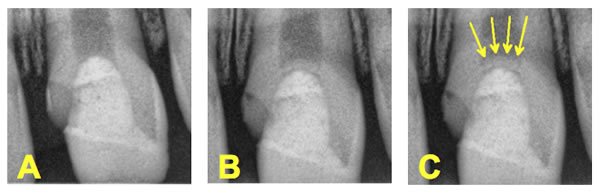

Évaluation clinique et radiographique à 3–4 semaines, 3 mois, 6 mois, 12 mois, puis chaque année (Swift et al., 2003).

Critères de succès radiologiques :

• Formation de dentine de réparation et pont dentinaire visible

• Développement normal continu de la racine pour les dents immatures

• Absence de calcification pulpaire

• Absence de résorption radiculaire interne

• Absence de parodontite apicale

Quels critères radiologiques permettent de distinguer un pont dentinaire vrai d’une calcification pulpaire dystrophique ?

Un vrai pont dentinaire après coiffage apparaît radiologiquement comme une opacité linéaire, continue, homogène, localisée en regard du site d’exposition, avec préservation de la chambre pulpaire en dessous. Une calcification dystrophique (ou métaplasie calcique) présente une opacification diffuse, irrégulière, progressive, envahissant la chambre et les canaux, avec disparition progressive de l’espace pulpaire. La calcification dystrophique est un signe d’échec biologique à long terme, même en l’absence de douleur.